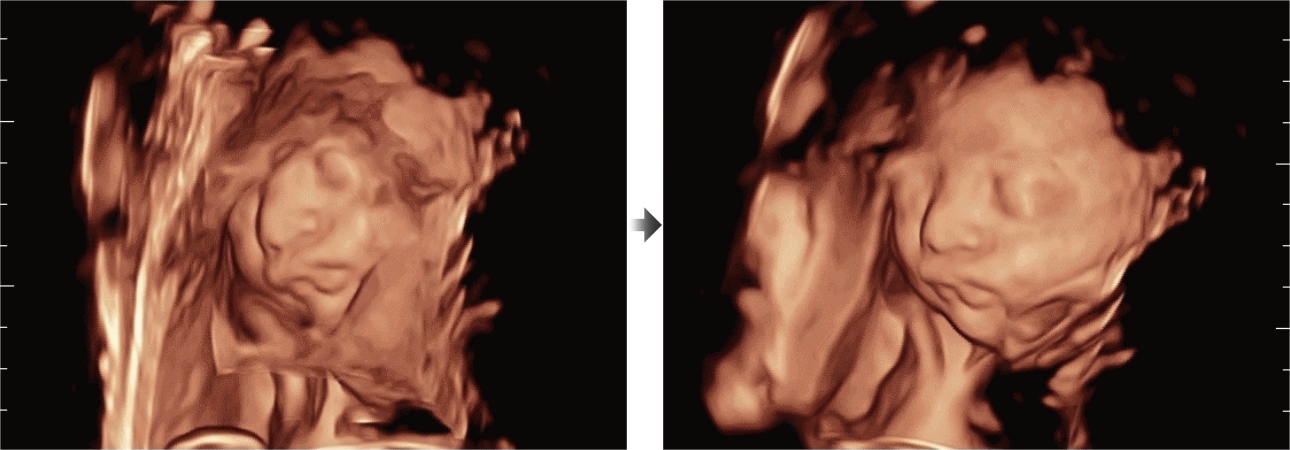

Oprócz uzyskiwania jako?ci obrazu typowego dla aparatów klasy premium, Resona 7 rozszerza mo?liwo?ci klinicznych badań USG dzi?ki rewolucyjnej funkcji V Flow, s?u??cej do oceny hemodynamiki naczyń, a tak?e najlepszej na rynku funkcji inteligentnego, automatycznego uzyskiwania p?aszczyzny na podstawie zestawów danych obj?to?ciowych 3D, umo?liwiaj?cej diagnozowanie stanu Centralnego Uk?adu Nerwowego u p?odu. Aparat Resona 7 ??czy w sobie najbardziej intuicyjn?, wielodotykow? obs?ug? za pomoc? gestów oraz wszystkie kluczowe funkcje kliniczne, co sprawia i? jest prawdziwym liderem we wprowadzaniu innowacji w ultrasonografii.